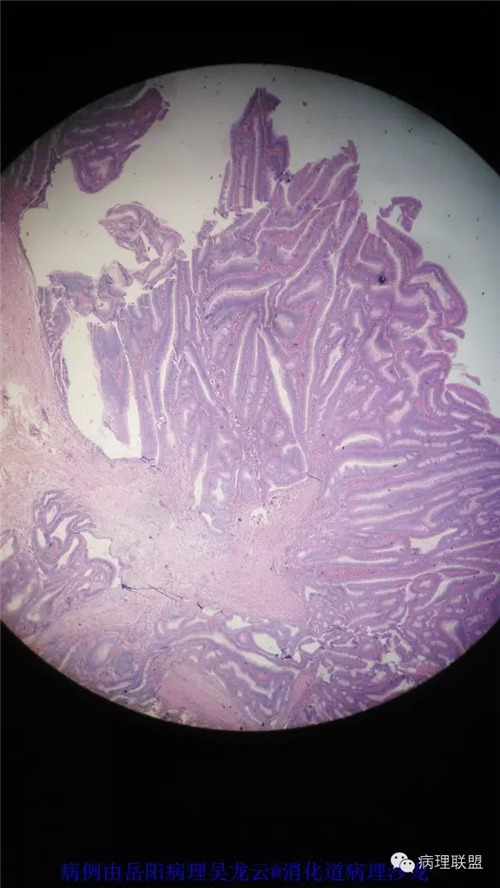

病例2

女性,60岁,结肠腺瘤活检。有一灶腺体突破粘膜肌,腺体无明显异形。

(注:病例由岳阳病理吴龙云提供 致谢!)